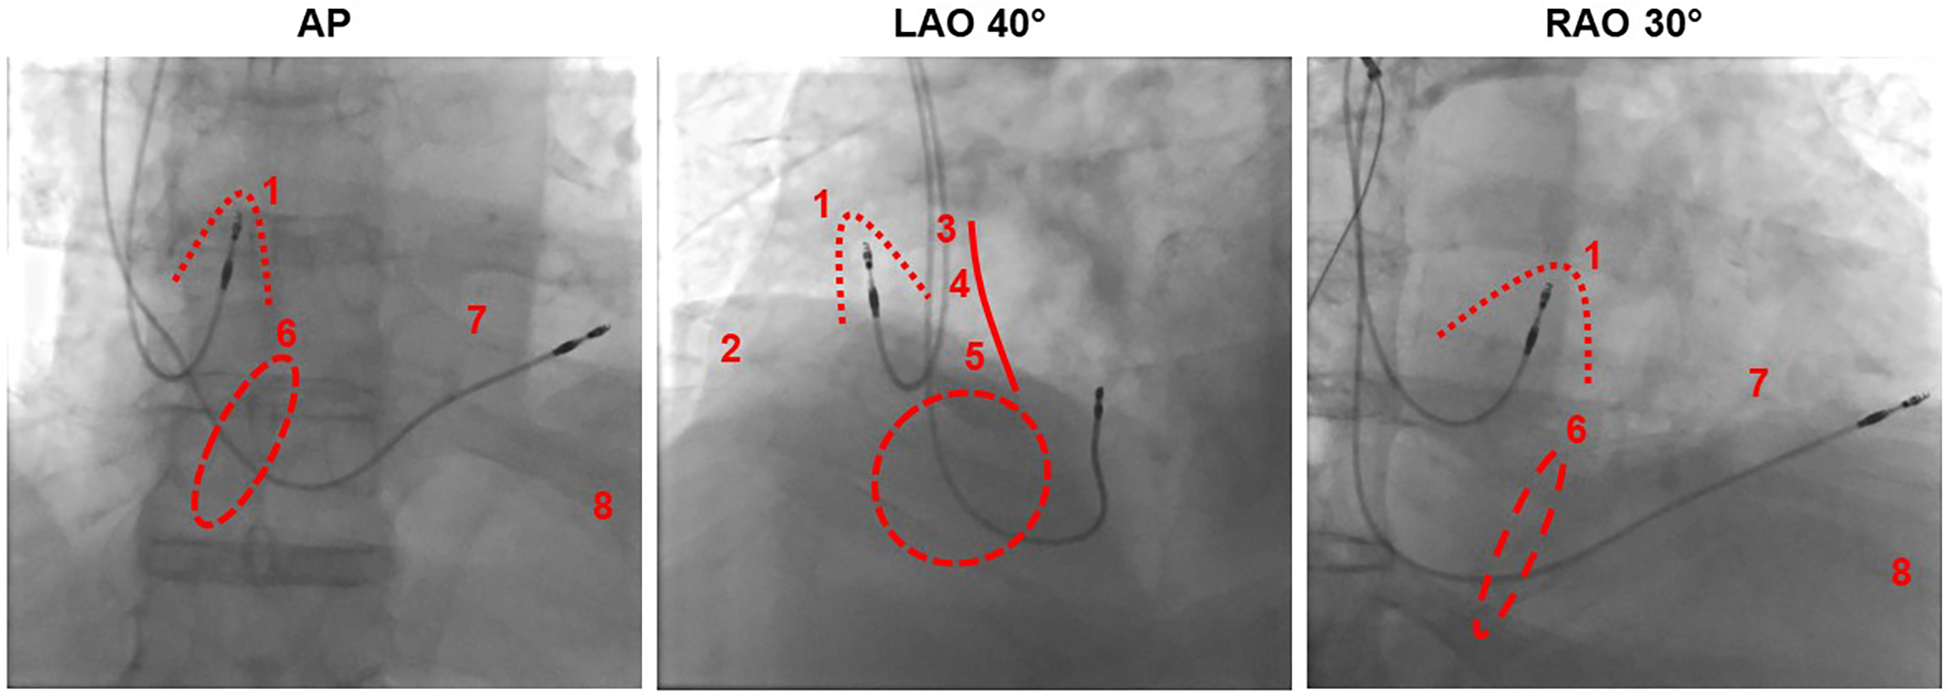

The positioning of the right atrial electrode in the right atrial appendage (RAA) is usually the first choice for implantation as it is relatively simple, even for an inexperienced clinician, and there is a low dislocation rate in this position. Another advantage is that good sensing and stimulation values are usually achieved here. Furthermore, the correct position of the electrode can be fluoroscopically verified during implantation (Figure 2).

Fluoroscopic imaging of atrial lead positioning in the right atrial appendage from different projections in relation to different pacing sites. AP, anterior-posterior; LAO, left anterior oblique; RAO, right anterior oblique. Dotted line: right atrial appendage, dashed line: tricuspid valve, solid line: atrial septum. (1) Right atrial appendage, (2) right atrial free wall, (3) Bachmann bundle, (4) high septal, (5) low septal, (6) his bundle near the tricuspid anulus, (7) right ventricular high septal, (8) right ventricular apical.